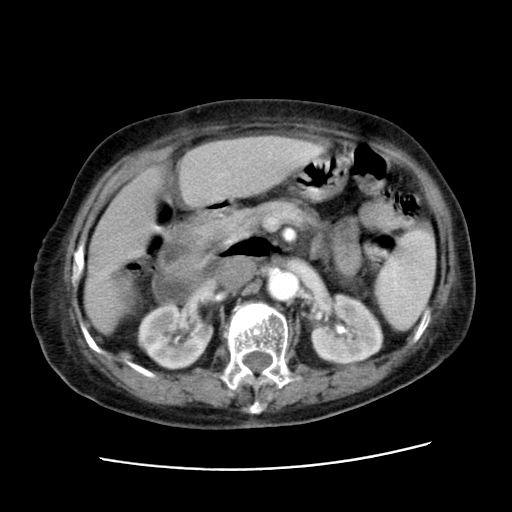

女,77.无不适

肝脏变异、异位胆囊,肝右叶肝内胆管结石并肝内胆管扩张。

肝右叶肝内胆管结石并肝内胆管扩张。

肝右叶肝内胆管结石并肝内胆管扩张

胆总管扩张

肝右叶肝内胆管结石并肝内胆管扩张。胆总管下段梗阻,考虑壶腹部占位。

右侧肝内胆管局限性扩张,其内密度不均匀,扩张的胆管壁增厚,考虑肝内胆管炎合并结石可能性大